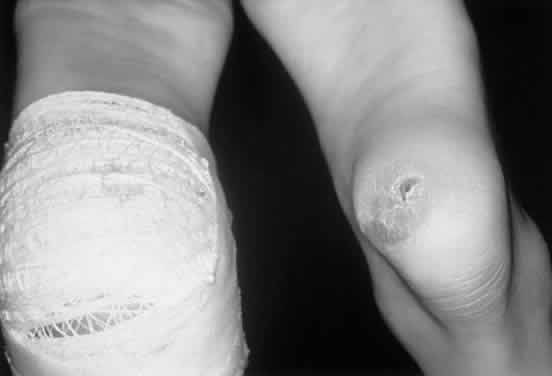

Onset of clinical signs and symptoms is later than in MLS II. The clinical course progresses more slowly, and survival into adulthood is possible.71,72 Most patients have been Ashkenazi Jews. Children usually present at about 3 years of age with joint stiffness, coarse facial features, and short stature.73 They have many of the features of Hurler syndrome but with a much slower clinical evolution and no mucopolysacchariduria. The arms and hands are involved most markedly, and carpal tunnel syndrome with wasting of the thenar eminence is common (Fig. 9). Aortic valve disease occurs in most cases. The pathology of MLS III is not well documented. Cultured fibroblasts have inclusion bodies similar to, but not as prominent as, MLS II cells.

Fig. 9. Child with mucolipidosis III. Note mild coarse facial features and joint contractures, most prominent in the hands.